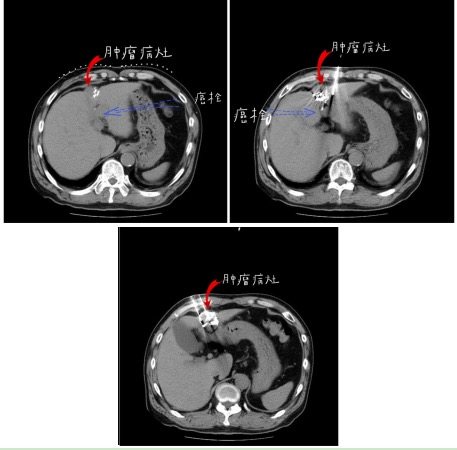

随 后,患者与沈阳市第六人民医院肿瘤介入综合科行肝组织间粒子植入,及门脉癌栓内粒子植入治疗,共植入37颗粒子,术后恢复良好出院。2020年4月8日复 查,肝增强MRI显示,病灶较前缩小,病灶内无明显强化,提示癌灶已坏死,门脉左右及主干支均通畅,肝门部及腹膜后淋巴结较前缩小。AFP 6.74 ng/ml,已降至正常。

粒子植入术中定位

粒子植入手术术中穿刺

粒子手术后4个月复查